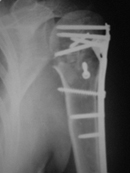

На консультативный прием обратилась женщина 42 лет, получившая 1.04.2007 бытовую травму:  закрытый оскольчатый перелом проксимального отдела левой плечевой кости со смещением отломков (b1_xr.jpg). 06.04.2007 оперирована в одном из отделений: открытая репозиция, накостный остеосинтез проксимального отдела левой плечевой кости. Выписана с заключительным диагнозом: а) основной: закрытый 4-х фрагментарный (по Ниру) перелом проксимального отдела левой плечевой кости, со смещением отломков; б) осложнения основного: нейропатия левого локтевого нерва;  в) сопутствующий: миокардитический миокардиосклероз ХСН 0-1.

В момент осмотра: нормостеническая конституция, по передней поверхности плечевого сустава – рубец. Рука в положении приведения. Отведение не более 10 град, дальнейшие движения с лопаткой до 20-25 град. Амплитуда сгибания-разгибания 10-15 град. Ротация отсутствует. Пальпаторно - выраженная болезненность над суставом, особенно в проекции клювовидного отростка. При попытках пассивных движений – боль. Рентгенограммы и результаты КТ приложены(b2(3)_xr.jpg, b1(6)_ct.jpg).

Диагноз: неправильно сросшийся в условиях накостного остеосинтеза оскольчатый перелом головки левой плечевой кости (11-С3.2), асептический некроз головки плечевой кости, смешанная артро-миогенная контрактура левого плечевого сустава; демиелинизирующая нейропатия левого локтевого нерва.

Анализ ситуации позволяет считать, что основными причинами контрактуры являются неправильная репозиция фрагментов головки (разворот кверху и кзади), асептический некроз головки плечевой кости (отчетливое склерозирование на СТ).

1.      Удаление металлоконструкции, эндопротезирование.

2.      Сохранение металлоконструкции с удалением выступающих за пределы головки винтов, релиз сустава, заполнение дефекта (b5_ct.jpg) на стыке метафиза и головки аутотрансплантатом для устранения «триггера», ранняя реабилитация.

3.      Удаление металлоконструкции, релиз, ранняя реабилитация.